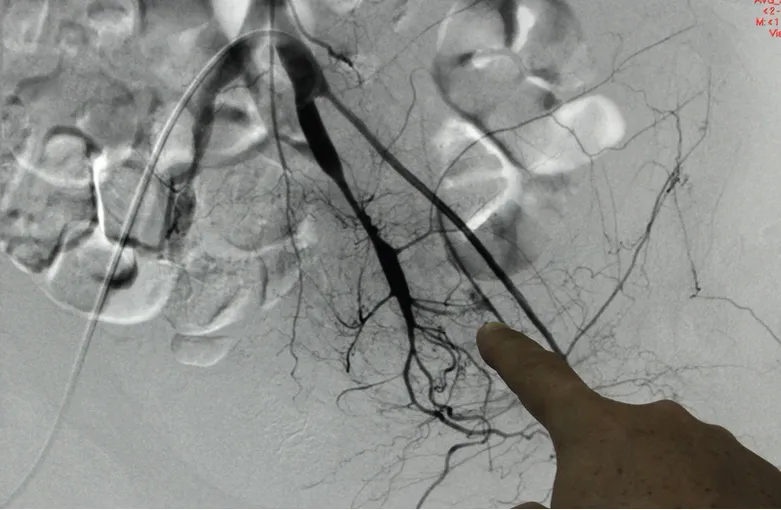

Vị trí chảy máu của ông T. qua hình ảnh DSA. Ảnh: Cao Viễn

Sau đó, các bác sĩ dùng DSA (phương pháp chẩn đoán hình ảnh kết hợp giữa chụp X-quang và xử lý số sử dụng thuật toán để xóa nền trên hai ảnh thu nhận được trước và sau khi tiêm chất cản quang vào cơ thể người bệnh nhằm mục đích nghiên cứu mạch máu trong cơ thể) để tìm nguyên nhân và giải quyết tình hình chảy máu. Sau khi xác định được vị trí máu chảy, các bác sĩ luồn ống thông đi từ động mạch đùi và dùng keo sinh học làm thuyên tắc mạch cầm máu. Sau hai ngày phẫu thuật, hiện ông T. tỉnh táo và có thể ăn uống, tình trạng chảy máu được giải quyết triệt để, huyết áp ổn định.